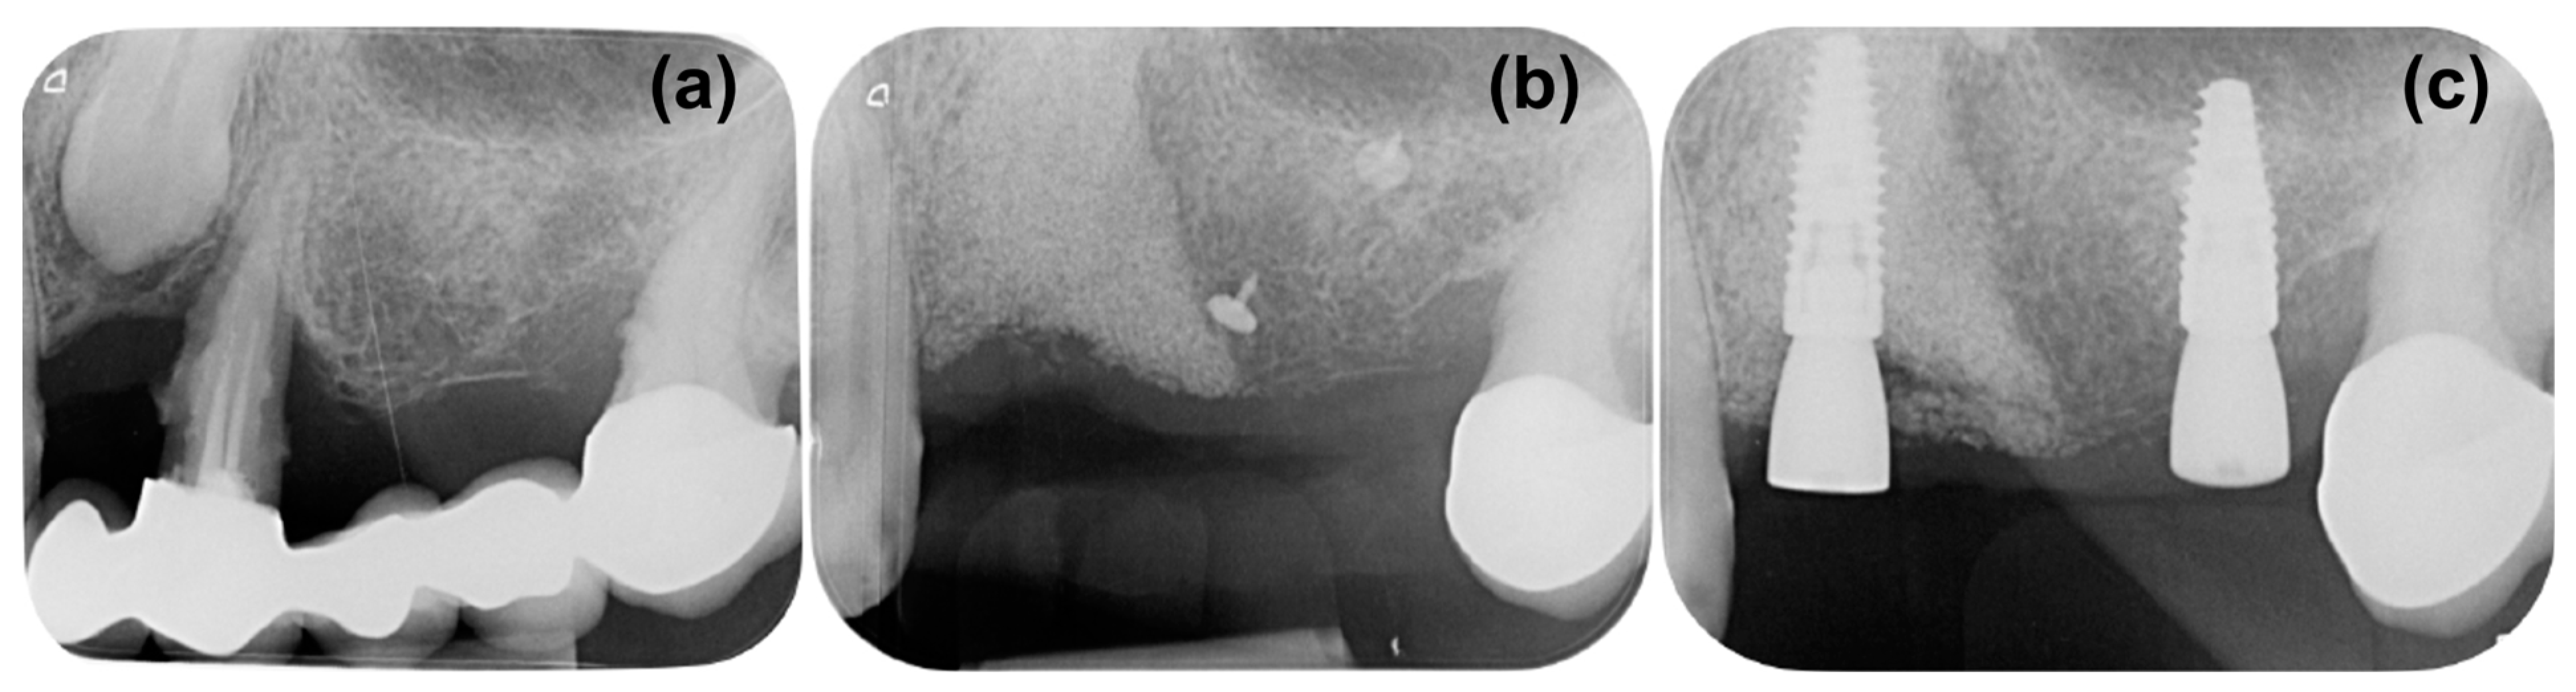

2. Case Presentation